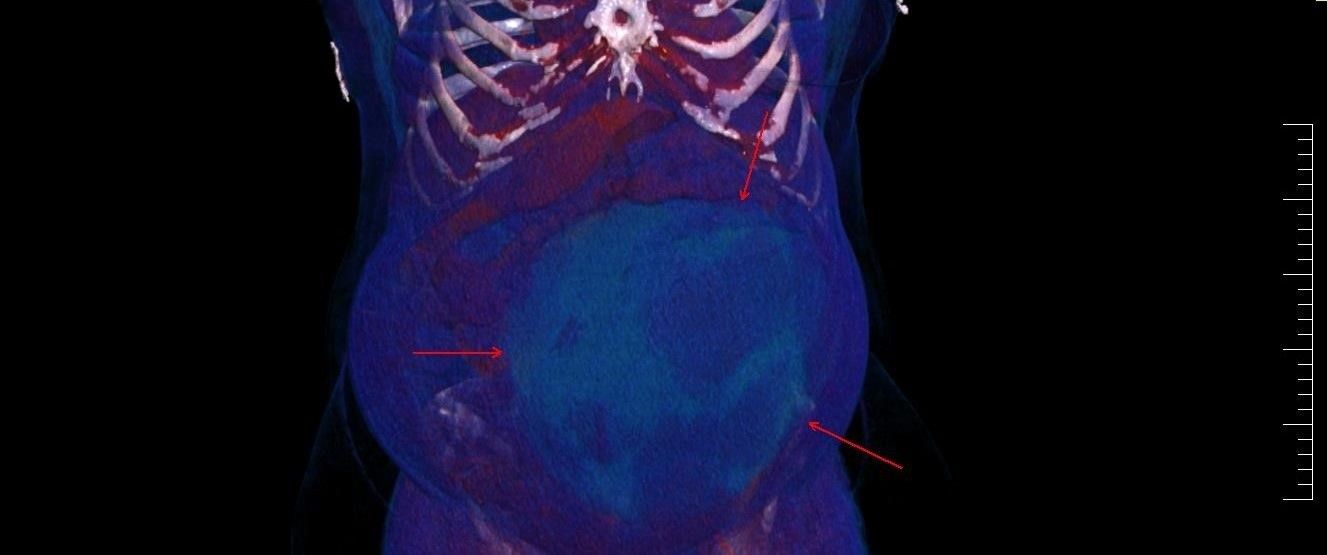

Potrivit reprezentanților Spitalului Militar de Urgență „Dr. Alexandru Augustin” din Sibiu, chistul ovarian de 4,5 kilograme a fost descoperit la o pacientă în urma unui consult ginecologic și a unor investigații în cadrul Laboratorului radiologie și imagistică medicală al Spitalului Militar de Urgență „Dr. Alexandru Augustin” din Sibiu.

„Un chist ovarian voluminos, de 4,5 kg, descoperit la o pacientă, în urma unui consult ginecologic și a unor investigații în cadrul Laboratorului radiologie și imagistică medicală al Spitalului Militar de Urgență „Dr. Alexandru Augustin” din Sibiu (Spital Militar Sibiu – n.red.), a fost operat cu succes de colegul nostru, Remus Maxim, medic primar obstetrică-ginecologie. Existând suspiciunea de neoplasm, medicul din cadrul Compartimentului Ginecologie din Secția Chirurgie Generală a luat decizia de a extrage formațiunea chistică în întregime, operația fiind un succes”.

Postarea a fost însoțită și de imagini pentru a arăta cum se poate schimba conformația corpului, dar și cum arată un chist în organism.